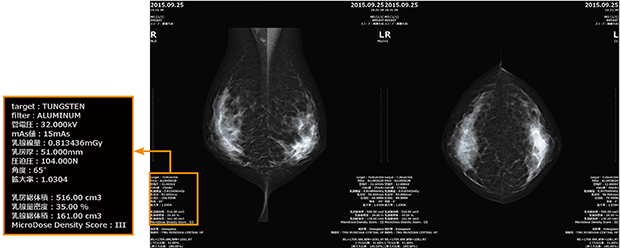

撮影条件とともに,スペクトラルイメージングによる乳腺密度がDICOM情報として表示される。

診断価値を高めるシングルショットスペクトラルイメージング

MicroDose SIのもうひとつの大きな特長が“シングルショットスペクトラルイメージング”である。通常の臨床画像の撮影だけで,追加撮影をすることなくスペクトラル情報を得ることができる。装置本体に搭載された乳腺量自動定量測定ソフトウエア“Breast Density Measurement”により乳腺密度情報が自動算出され,DICOM情報として画像とともに転送される。乳腺密度は3D解析により測定が行われ,乳房総体積,乳腺総体積,乳腺量密度,Density Score(Ⅰ〜Ⅳ)が画像上に表示される。精度誤差は2%以内とされており,マンモグラフィ読影において重要な情報である乳腺密度を,従来の視覚評価だけでなく,定量評価できることが期待される。

乳腺密度情報はDICOMのプライベートタグとして出力されるため,一次読影を依頼する際には,検診カルテに記載して乳腺外科医と情報を共有し,読影の参考としてもらっている。長谷川技師は,「まだ症例数も少ないので,この数値が従来の視覚評価とどの程度の相関があるかを検討していく必要があります」と述べる。また,渡邊技師長は,「Density Scoreについては,医師と技師で話し合ってどのように活用していくかの院内ルールを検討し,症例を重ねてグループ内の勉強会でも発表したいと思います。ほかのマンモグラフィ装置ではできない低線量撮影,そして乳腺密度情報をフル活用し,今後の検査に役立てていきます」と,展望を語った。